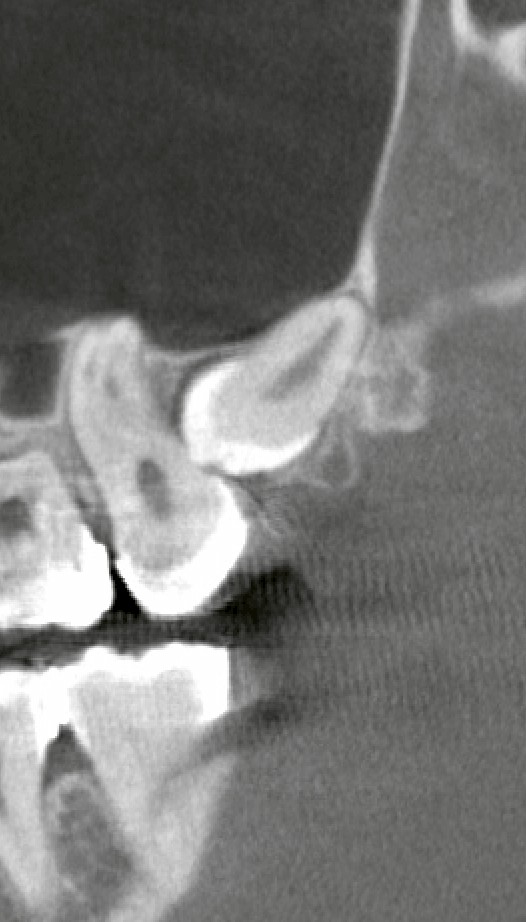

CTで見ると、親知らずの根の先が上顎洞にかなり近接していました。

上顎洞に近いだけなら、慎重に操作すれば問題なく終わることも多いです。

上顎の抜歯は割とすぐ終わるのですが、今回のケースは完全埋伏しているケースであり、上顎洞に近接+矯正器具により視野確保困難などの要素が加わり、慎重に時間をかけながら実施しました。

抜歯後に確認すると、上顎洞側に数ミリ程度の交通が疑われる所見がありました。

大きな穴ではありませんが、細菌が入り込むには十分なサイズになり得ます。